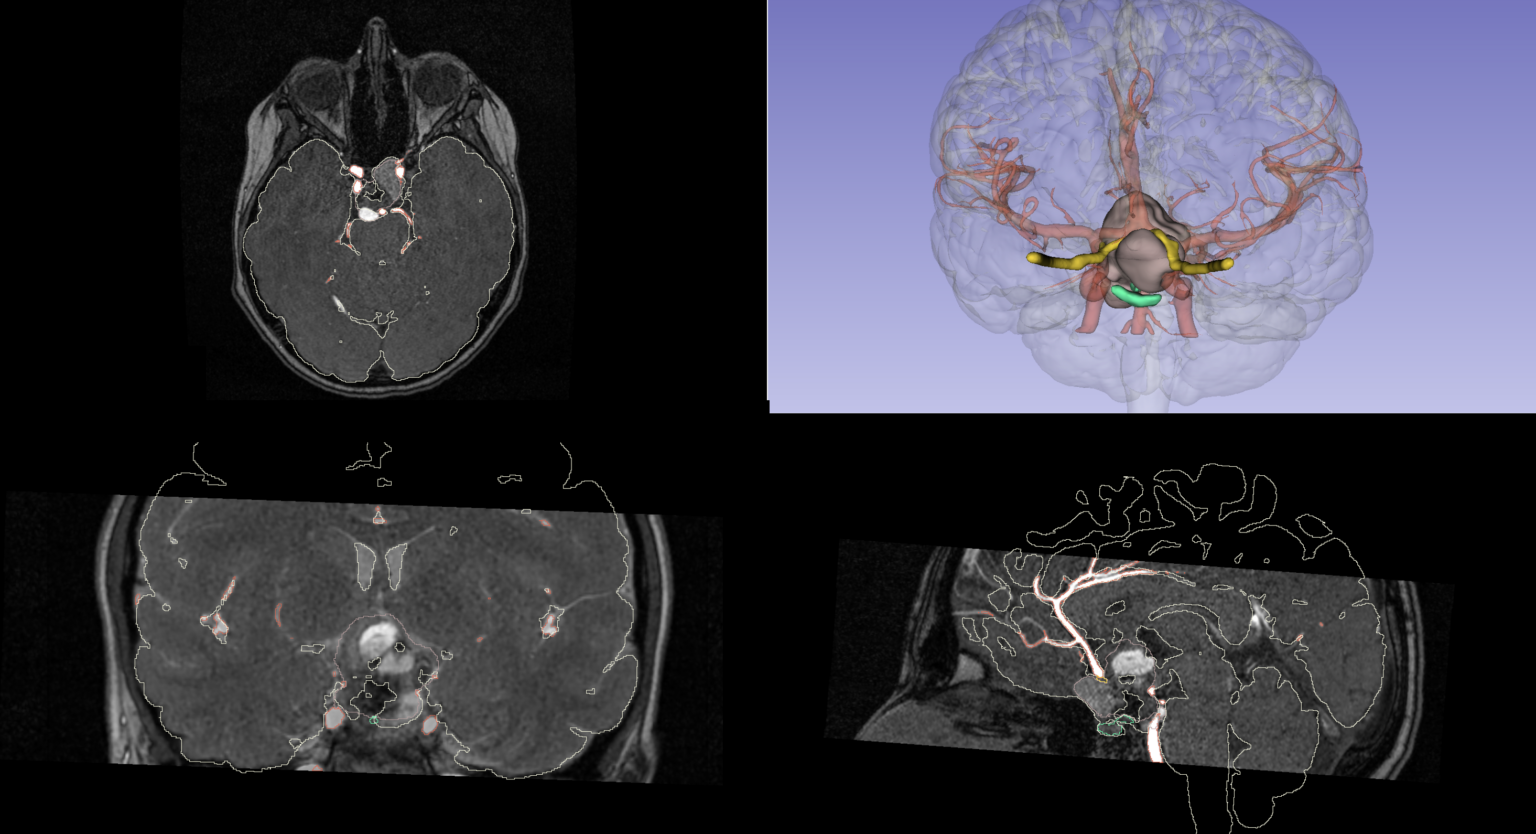

We are pleased to share a new scientific contribution that explores a multidisciplinary and technologically advanced approach to the treatment of pediatric craniopharyngioma—a rare benign

ESPU 2025 Award: the collaboration between Printmed-3D and Buzzi Children’s Hospital proves once again to be a winning partnership

A Rare Tumor, an Innovative Solution: The Power of Virtual Reality and 3D Printing